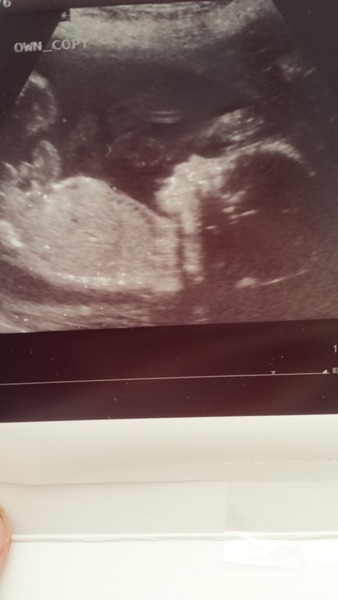

Had my scan this morning it was just lovely. Beanie kept yawning! Grin